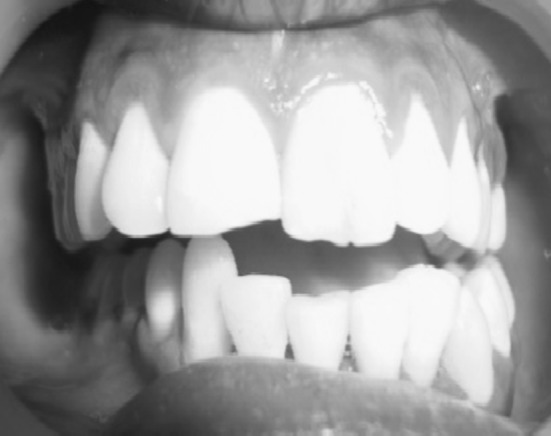

Fig. 1.

Deranged occlusion

Fig. 9.

6 month post operative occlusion